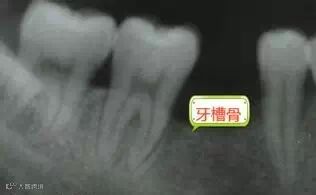

牙缺失后正常咬颌力对牙槽骨的生理性刺激将不复存在,牙槽骨均会出现不同程度的废用性萎缩,并且会给后期假牙修复及维持口腔颌面部的平衡和稳定带来巨大困难。